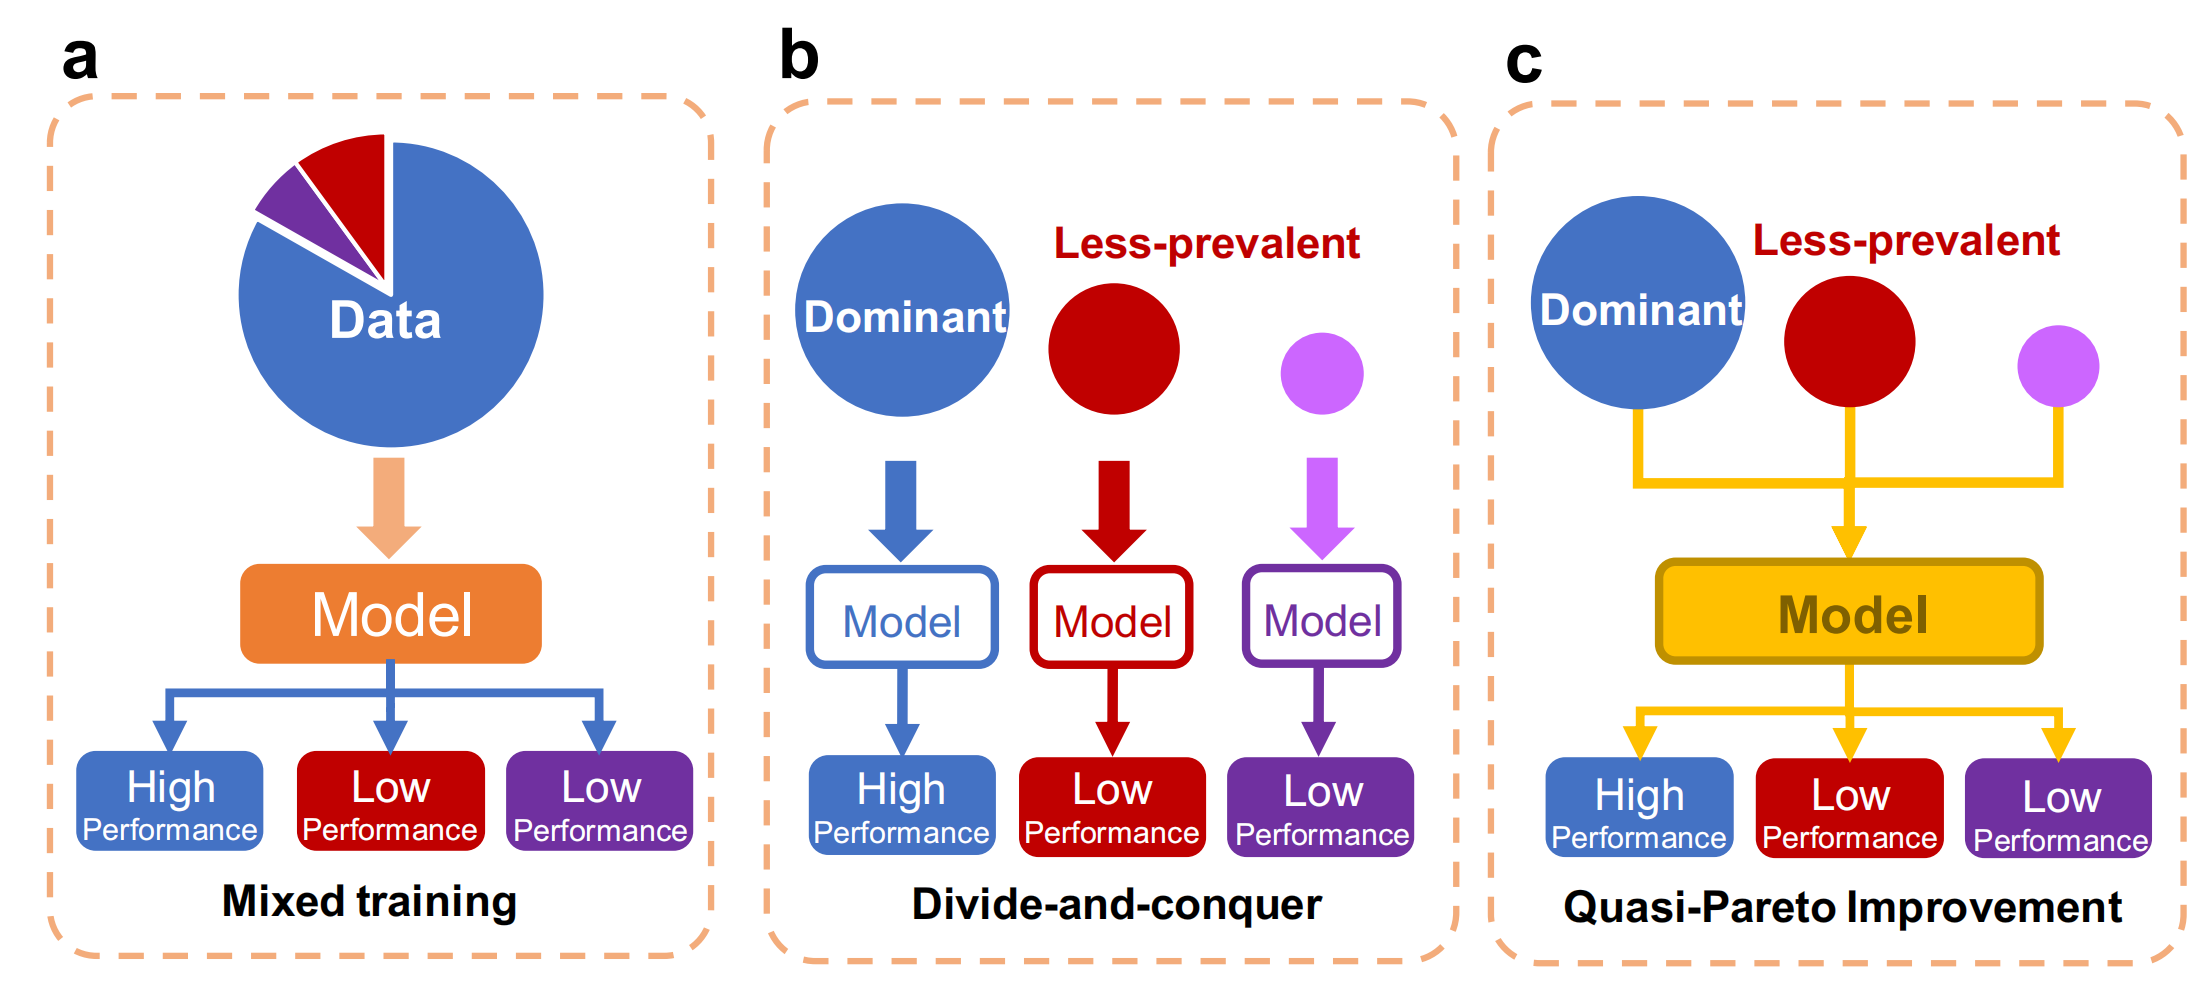

Fig. 1 展示了处理较少见亚群(less-prevalent subgroups)的三种不同方法:

a. 混合训练(Mixed training):这种方法涉及使用来自多个亚群的混合数据进行训练。其目标是训练一个能够在所有亚群上表现良好的AI模型。混合训练的潜在风险是模型可能会忽视较少见亚群的特征,因为这些特征在整体数据中所占比例较小。

b. 分而治之(Divide-and-conquer):与混合训练不同,分而治之方法将不同亚群的数据作为独立的训练集,并分别为每个亚群训练模型。这种方法可以确保每个亚群都有足够的机会学习其特定特征。然而,较少见的亚群通常样本量不足,可能无法支持AI模型的训练,导致性能不佳。

c. 准帕累托改进(Quasi-Pareto Improvement, QPI)方法:QPI方法旨在改善不平衡亚群的预测性能,同时保持模型在整体人群上的预测性能。这是通过结合多任务学习和领域适应技术来实现的。QPI方法试图在不损害主导亚群性能的前提下,提升较少见亚群的性能,从而实现更公平的模型预测。

在Fig. 1中,每种方法旁边都有一个模型和数据的图示,表示不同方法对模型训练和预测性能的影响。混合训练可能导致较少见亚群的性能较低,因为它可能会被主导亚群的特征所淹没。分而治之可能在较少见亚群上表现更好,但由于样本量不足,可能仍然存在性能限制。而QPI方法则旨在提升所有亚群的性能,特别是通过改善较少见亚群的特征学习,同时保持对主导亚群的高性能。

总结来说,Fig. 1强调了在AI模型开发中处理不同亚群的重要性,并提出了QPI作为一种创新方法,以提高模型在所有亚群上的公平性和准确性。